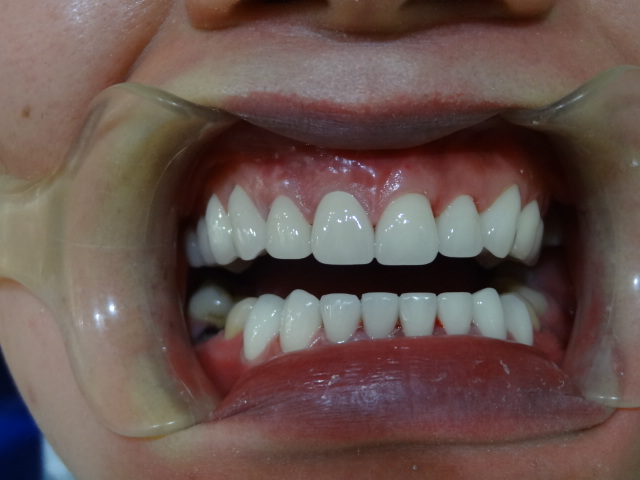

術(shù)后

做完超聲波洗牙第7天我就能正常吃飯咬骨頭了,以后每年都要去洗一次。

超聲波洗牙第七天